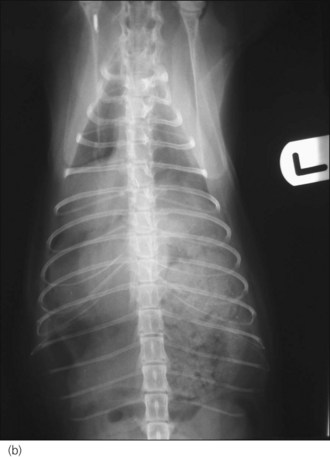

image

Figure 28.3 Right lateral thoracic radiograph of a dog showing traumatic tension pneumothorax. The dog underwent cardiopulmonary arrest just prior to arrival at the hospital and the owner did not want resuscitation to be attempted.